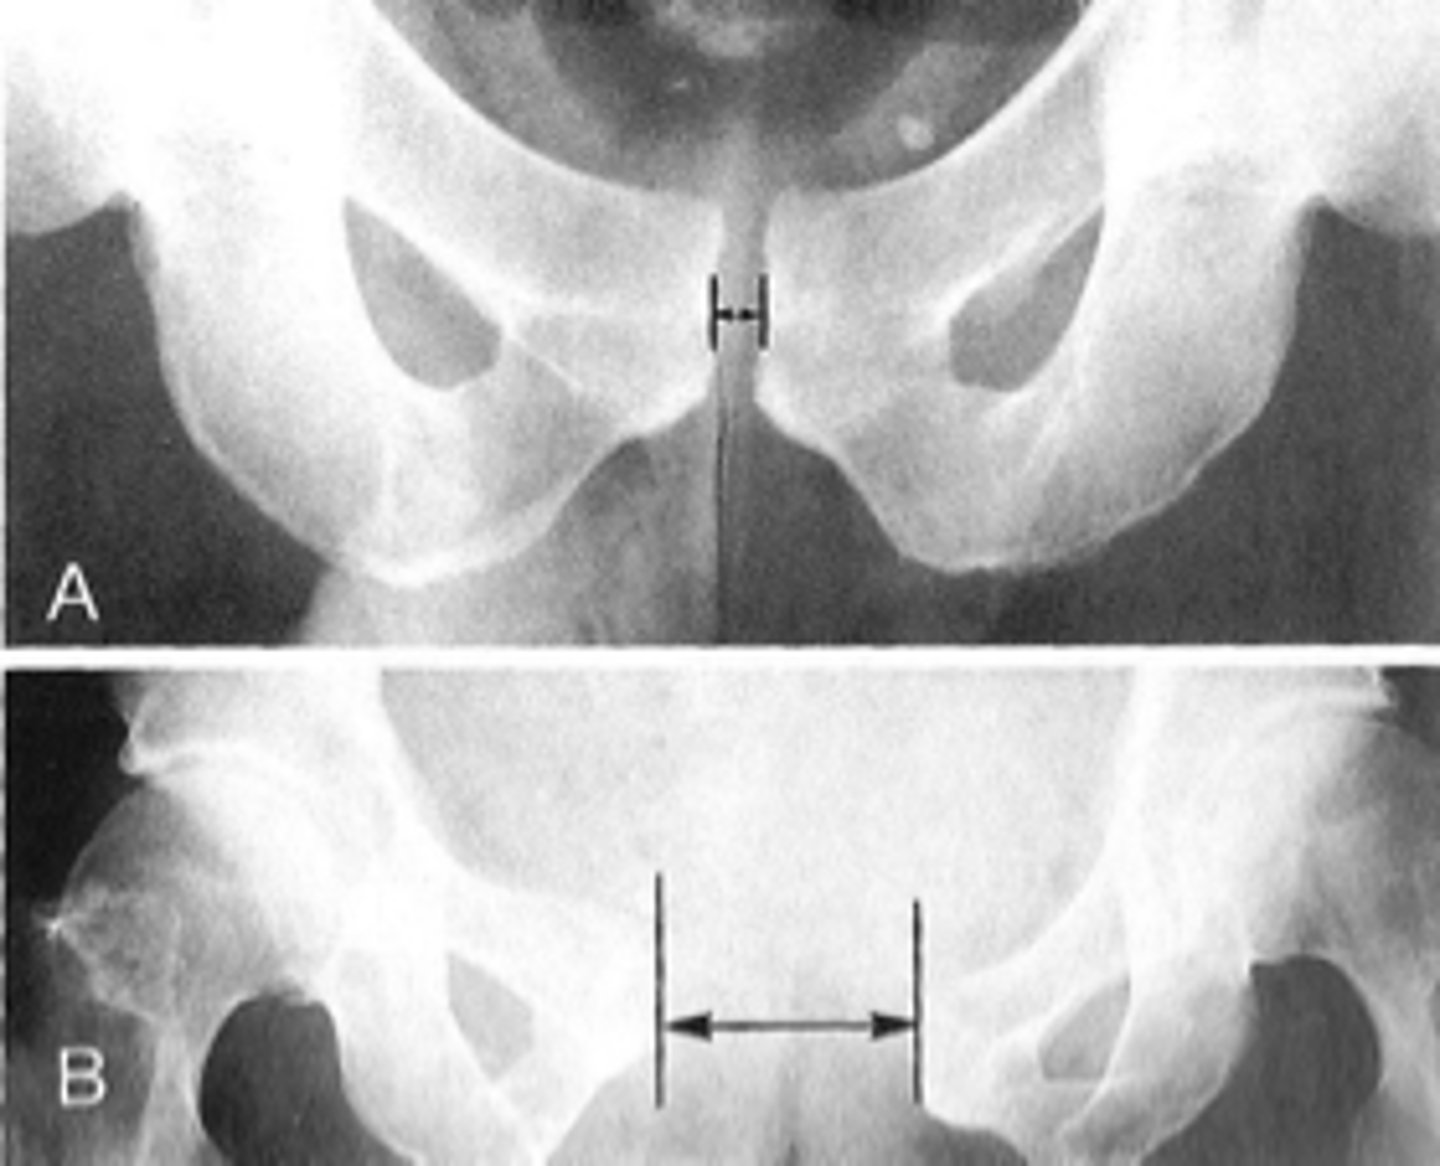

Symphysis pubis width

ID measurement

<p>ID measurement</p>

AP pelvis

What view is used to see the symphysis pubis width?

<p>What view is used to see the symphysis pubis width?</p>

Distance between opposing articular surfaces

Symphysis pubis width landmarks

<p>Symphysis pubis width landmarks</p>

8 mm

Maximum symphysis pubis width measurement in adults

<p>Maximum symphysis pubis width measurement in adults</p>

10 mm

Maximum symphysis pubis width measurement in children

<p>Maximum symphysis pubis width measurement in children</p>

Pregnancy/postpartum

The symphysis pubis width may be larger in _____

<p>The symphysis pubis width may be larger in _____</p>

Diastasis

Clinical significance of a widened symphysis pubis

<p>Clinical significance of a widened symphysis pubis</p>